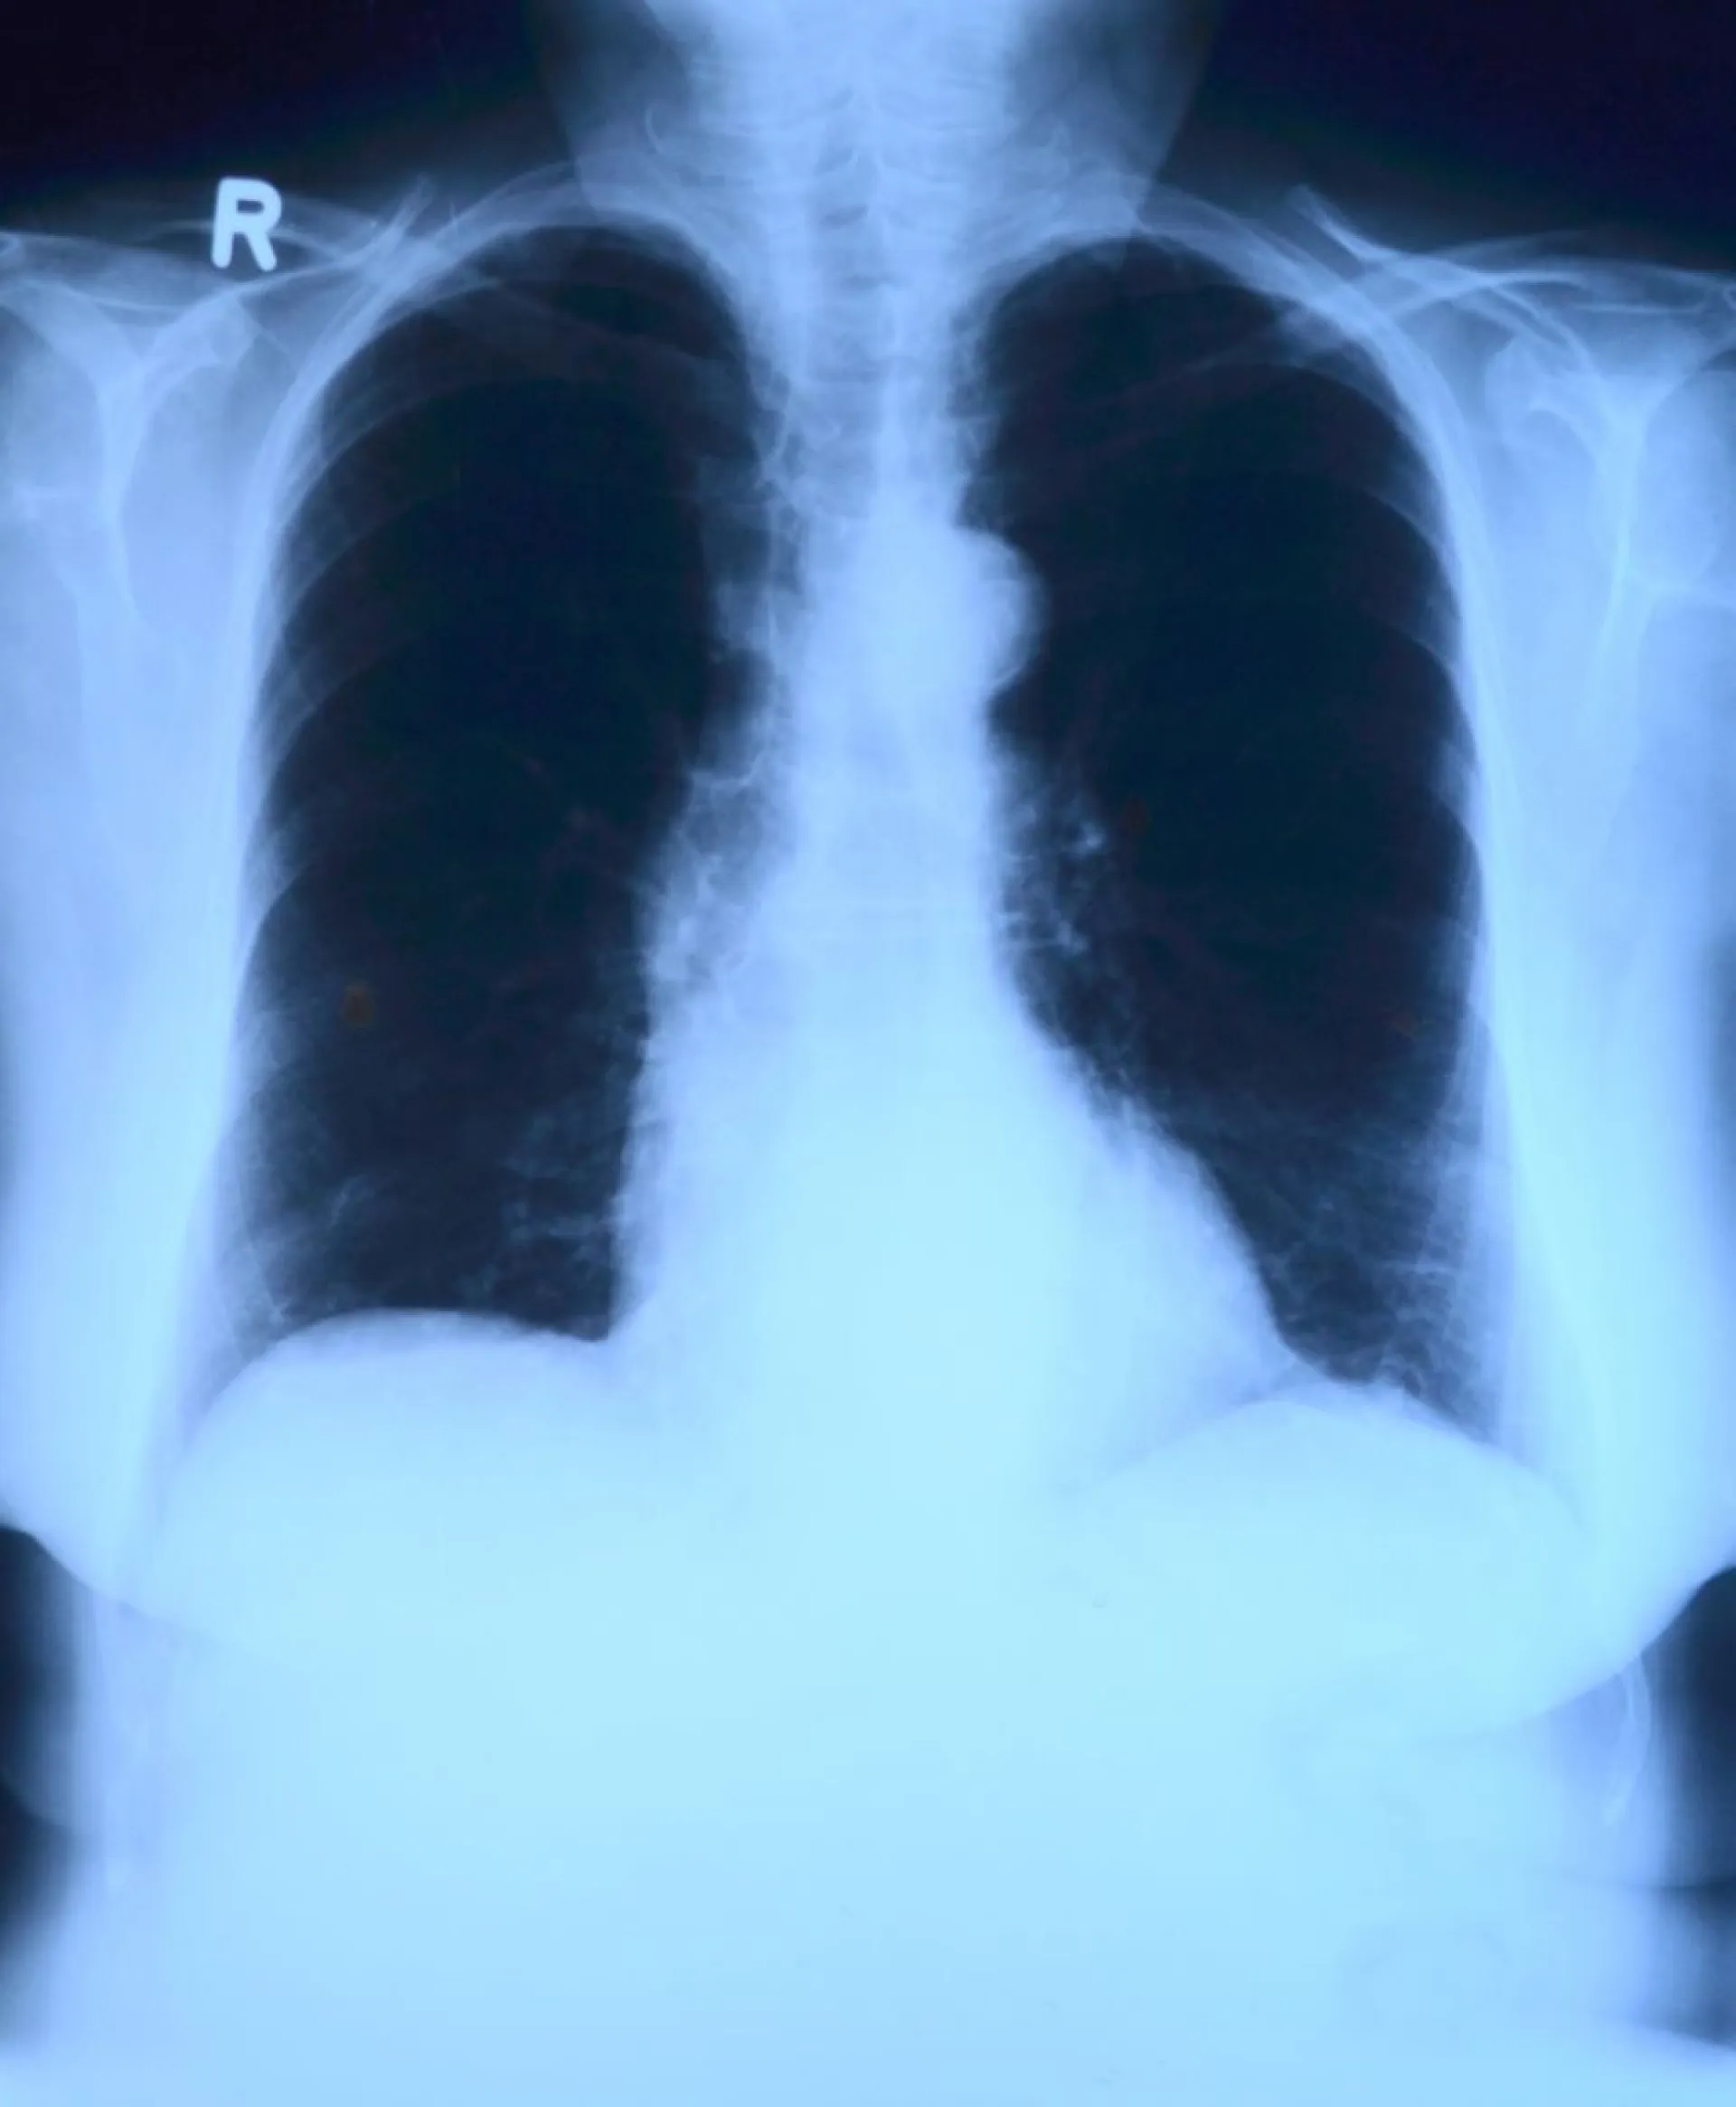

Наиболее эффективным и действенным средством ранней диагностики туберкулеза остаётся флюорографический осмотр. Делать флюорографию рекомендуется не реже одного раза в год, уточнили в Минздраве Алтайского края.